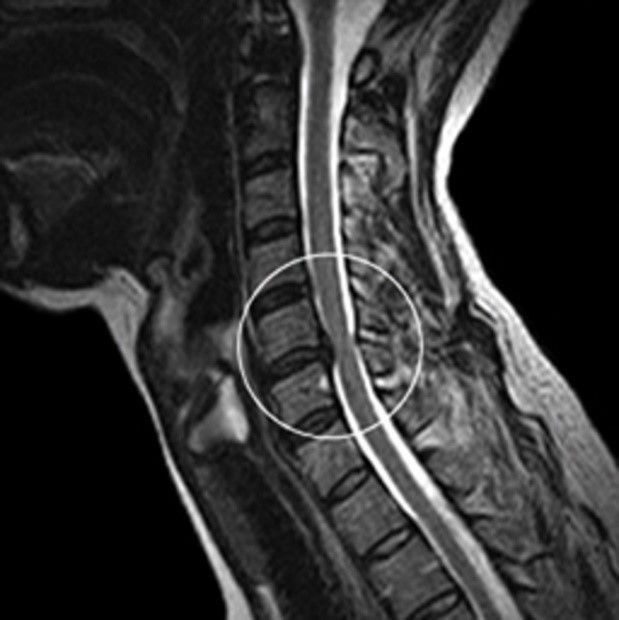

목디스크 증상 목디스크란 목 뼈 사이의 디스크가 원래의 자리에서 이탈하면서 신경을 누르거나 뼈조직이 비정상적으로 자라나 목을 지나가는 척추신경을 누르게 됨으로써 통증을 느끼는 질환입니다. 예전에는 40대 이상의 분들한테서 주로 나타나는 질환이었지만 요즘은 젊은 세대에도 흔하게 볼 수 있는 질환이 되었습니다.

목디스크가 심한 해당에는 어깨뿐만 아니라 팔과 손가락에도 저림을 동반한 고통을 느끼실 수 있다. 디스크의 수핵이 빠져나가거나 퇴행성 경추 척추증 및 경추관 협착증 등으로 척수가 눌리게 되면 대개는 팔의 힘이 빠지는 느낌을 받을 수 있다. 이러한 해당에는 팔을 머리 위로 들면 고통이 완화되는 해당이가 있는데 일시적일 뿐 목디스크의 전형적인 증상이니 꼭 정형외과에 방문하셔서 전문의에게 상담을 받아보시길 권장드린다.

목디스크 치료방법 중 신경성형술은 척추질환의 가장 흔한 비수술적 치료법입니다. 1mm 마이크로 카테터를 사용하여 신경통 부위의 유착을 찾는다. 그 후 신경성형술은 신경가소성을 사용하여 경우 부위를 치료하고 통증을 완화해요. 신경가소성에는 통증 감소 및 다른 치료법에 대한 접근을 포함하여 5가지 주요 이점이 있습니다.

목디스크 치료방법 중 수술치료 방법은 비수술적 치료가 효과가 없거나 디스크 신경 압력이 너무 높을 때 최후의 수단입니다. 사소한 치료조차 할 여지가 없습니다. 즉. 비수술적 방법을 고집하더라도 주변 정상 조직이 손상될 수 있습니다.

치료 방법에는 인공 대체물로 디스크 교체, 척추 유합술 및 전방 감압 및 유합 수술, 신경 감압 수술, 후궁 절제술 및 후궁 성형술이 있습니다. 무엇이든 치료하기 전에 전문가와 상의해야 해요. 적절한 진단이 우선되어야 합니다. 그리고 전문의와 상의 후 구체적인 치료법을 결정해야 해요.